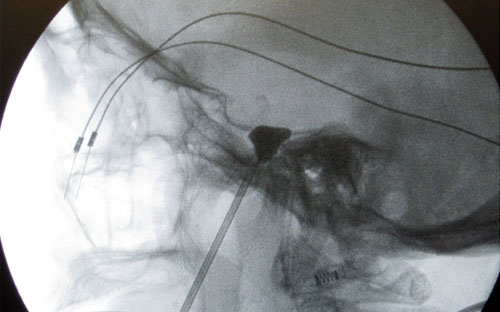

En el tractament percutani de la neuràlgia del trigemin s’aborda el gangli de Gasser, que és la zona anatòmica a on el nervi es divideix en les seves tres branques terminals. Aquest  gangli està situat dins del crani sobre la base. A la base cranial hi ha uns forats que permeten que els nervis que surten del cervell arribin a les estructures de la cara. Un d’aquests forats és el forat oval situat just sota del gangli de Gasser i per on surt la tercera branca del nervi trigemin. S’aprofita aquesta disposició anatòmica per accedir al gangli de Gasser puncionant des d'un punt situat 2-2,5 cm per fora de la comissura bucal. El pacient està situat en decúbit supí (panxa enlaire) amb una discreta extensió posterior del coll. Hi ha  unes referències anatòmiques i la punció es fa amb control de Rx. En el moment de la punció el pacient està anestesiat.

En aquest procediment la interrupció del nervi és per compressió mecànica del gangli amb un baló. La punció del gangli és igual a la descrita a dalt, a través de la agulla de punció s’introdueix una catèter que porta un globus a la punta i que s’infla dintre del gangli amb  una mescla de sèrum i  contrast radiològic (total 1 cc) i  es manté la compressió d’un a quatre minuts.